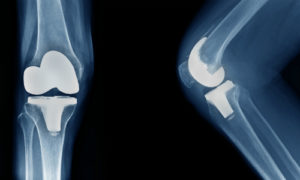

Surgeons carry out either a partial (medial, lateral or patello-femoral) or total knee replacement. Which surgery you receive depends on your symptoms and x-ray findings and would follow a discussion with your surgeon about the expected outcomes of each.

A padded bandage dressing is applied to the knee immediately after surgery and then reduced at around 48 hours. Patients are encouraged to get out of bed and walk with the help of the physiotherapists on the day of surgery or the following day, helping to prevent stiffness and maintain healthy circulation. To reduce the risk of thrombosis you would also likely be given blood thinning medication. An x-ray is carried out after surgery to check the position of the implants and routine blood tests are done around 24 hours post-operatively. You’ll be given pain relieving medication to manage your recovery.

As an outpatient you would have physiotherapy and be reviewed in clinic a few weeks later. Initially, as activity increases the knee can be sore, but with appropriate medication and gentle exercise, your recovery should proceed smoothly. You’ll be recommended to have a check-up x-ray 12 months after surgery as well as prosthesis monitoring.